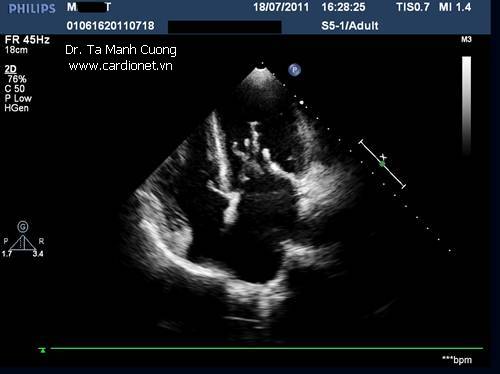

Hình ảnh sùi van hai lá do viêm nội tâm mạc nhiễm khuẩn

Ở mặt cắt siêu âm khác trên cùng bệnh nhân: